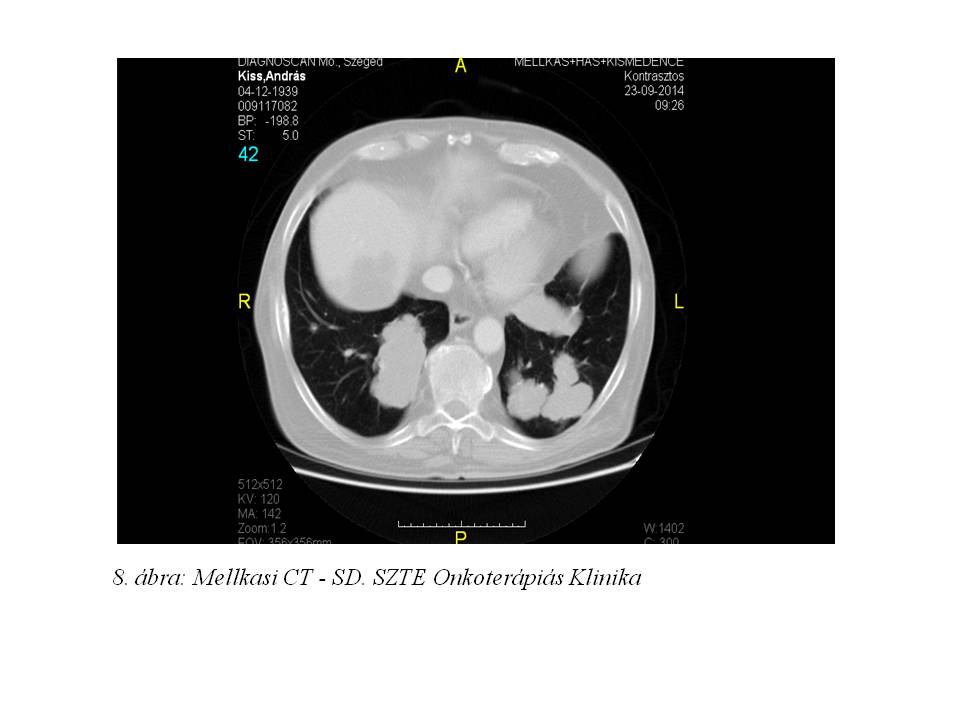

A 3 havonkénti tumorválaszt leíró vizsgálatok eddig SD-t igazoltak (8. ábra, 9. ábra). Eddig a beteg 9 ciklust kapott, ami bíztató a hosszú távú túlélés viszonylatában. Amennyiben a soros képalkotó vizsgálatok a betegség előrehaladását véleményezik, betegünk jó általános állapota még mindig lehetővé tesz klinikai vizsgálatban való részvételt, mellyel további hónapokat (vagy akár éveket?) nyerhet.